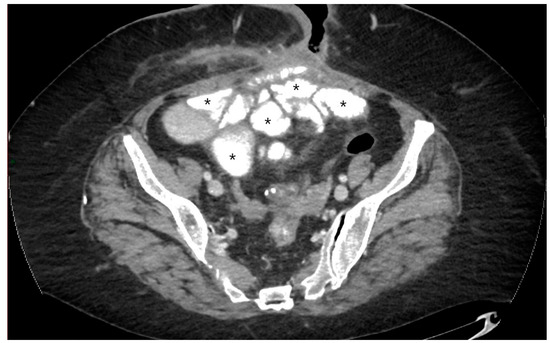

5.3. Fistulising/Perforating Subtype